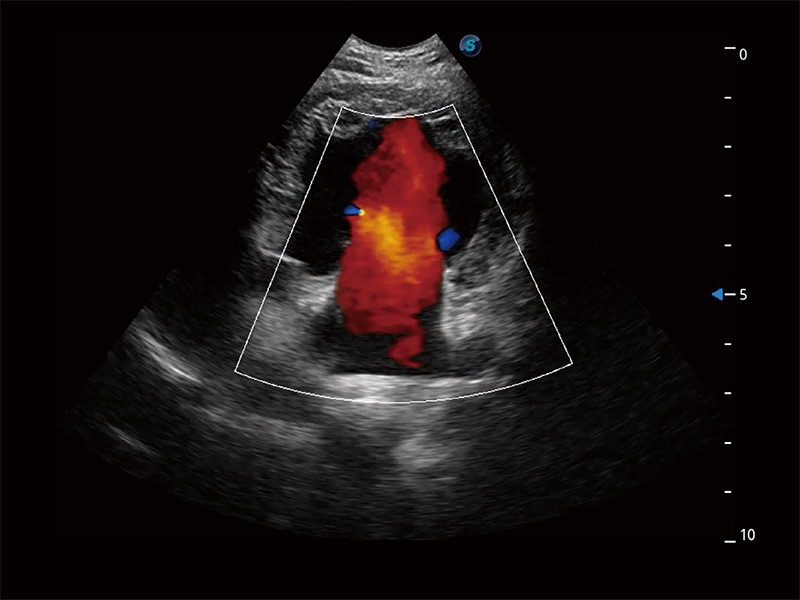

非线性融合造影成像充分利用谐波和基波信号,为难以观察的血流进行增强显像。可用于线阵、凸阵、微凸阵、相控阵探头。

ProPet 80 配备了丰富的心脏探头群、先进的成像技术和专业的心脏测量工具,可帮助动物医生为不同体型和生理结构的动物提供心脏和心肌功能的全面评估。